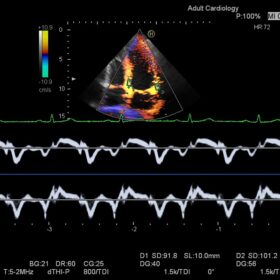

Ultrasound HI VISION Ascendus – Image Gallery and Videos

Cardio 2D and Color mode